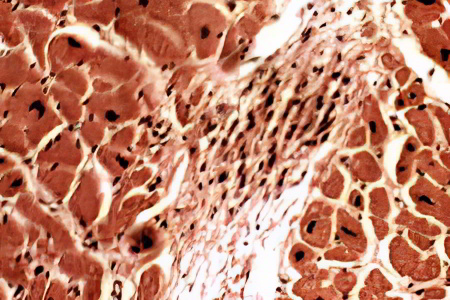

Гранулёма — это локализованные разрастания клеток соединительной ткани воспалительного характера, проявляющиеся в виде небольших узелков. Их причины могут быть различными. Существуют инфекционные и неинфекционные гранулёмы, а также гранулёмы с неустановленной причиной.

Инфекционные гранулёмы формируются при заболеваниях, таких как туляремия, бешенство, брюшной и сыпной тиф, вирусный энцефалит, туберкулёз, ревматизм, сифилис и других. Неинфекционные гранулёмы возникают из-за медикаментозного воздействия (например, при олеогранулёматозной болезни и гранулёматозных гепатитах) или профессиональных заболеваний, связанных с пылью (такими как биссиноз, асбестоз, талькоз и другие). Они также могут образовываться вокруг инородных тел. Гранулёмы, возникающие при болезнях Хортона и Крона, а также при саркоидозе, обычно классифицируются как гранулёмы с неясной этиологией.